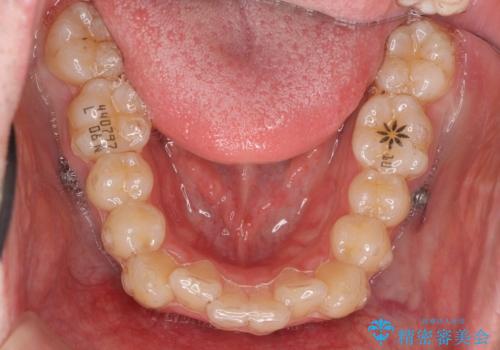

- インビザライン

- 前歯のがたつきを主訴に来院。

歯を抜かずに、奥歯を後ろに下げ、歯の両側をわずかに削って並べました。

奥歯を後ろに下げるのに、上下左右に矯正用ミニスクリューを入れています。

そのまま並べると戻りやすいのと、口元が出てしまうためです。